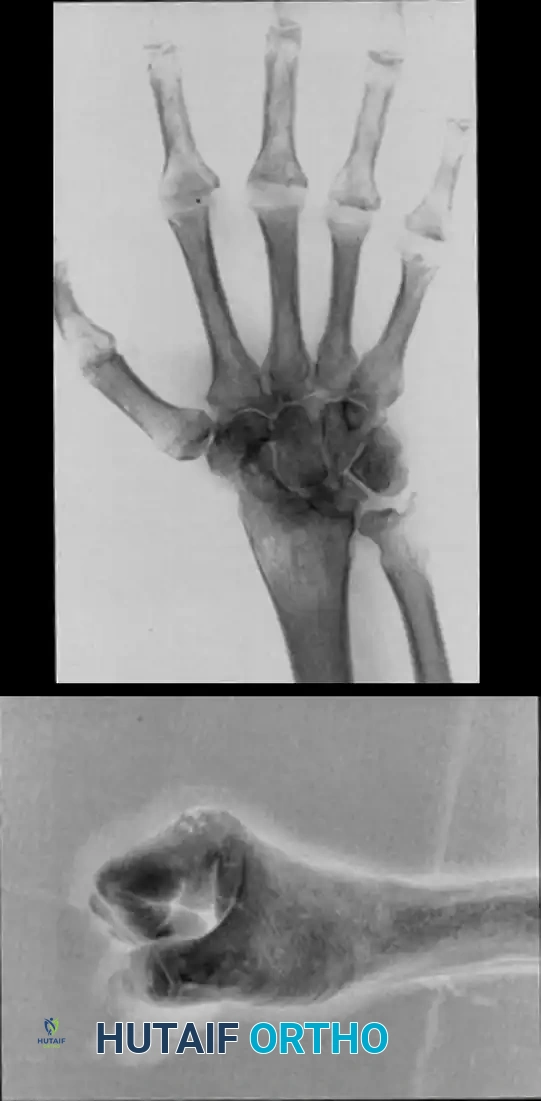

Radiographic Outcomes of Trapeziometacarpal Procedures

When simple trapezium excision is performed without robust ligamentous suspension, proximal migration (settling) of the first metacarpal is a known biomechanical consequence.

FIGURE 73-35: Radiographic progression at 2 months and at 3 years after simple trapezium excision (arrow). Note the progressive metacarpal settling and resultant scaphometacarpal space narrowing; however, clinically, the thumb often remains functionally stable despite this radiographic appearance.